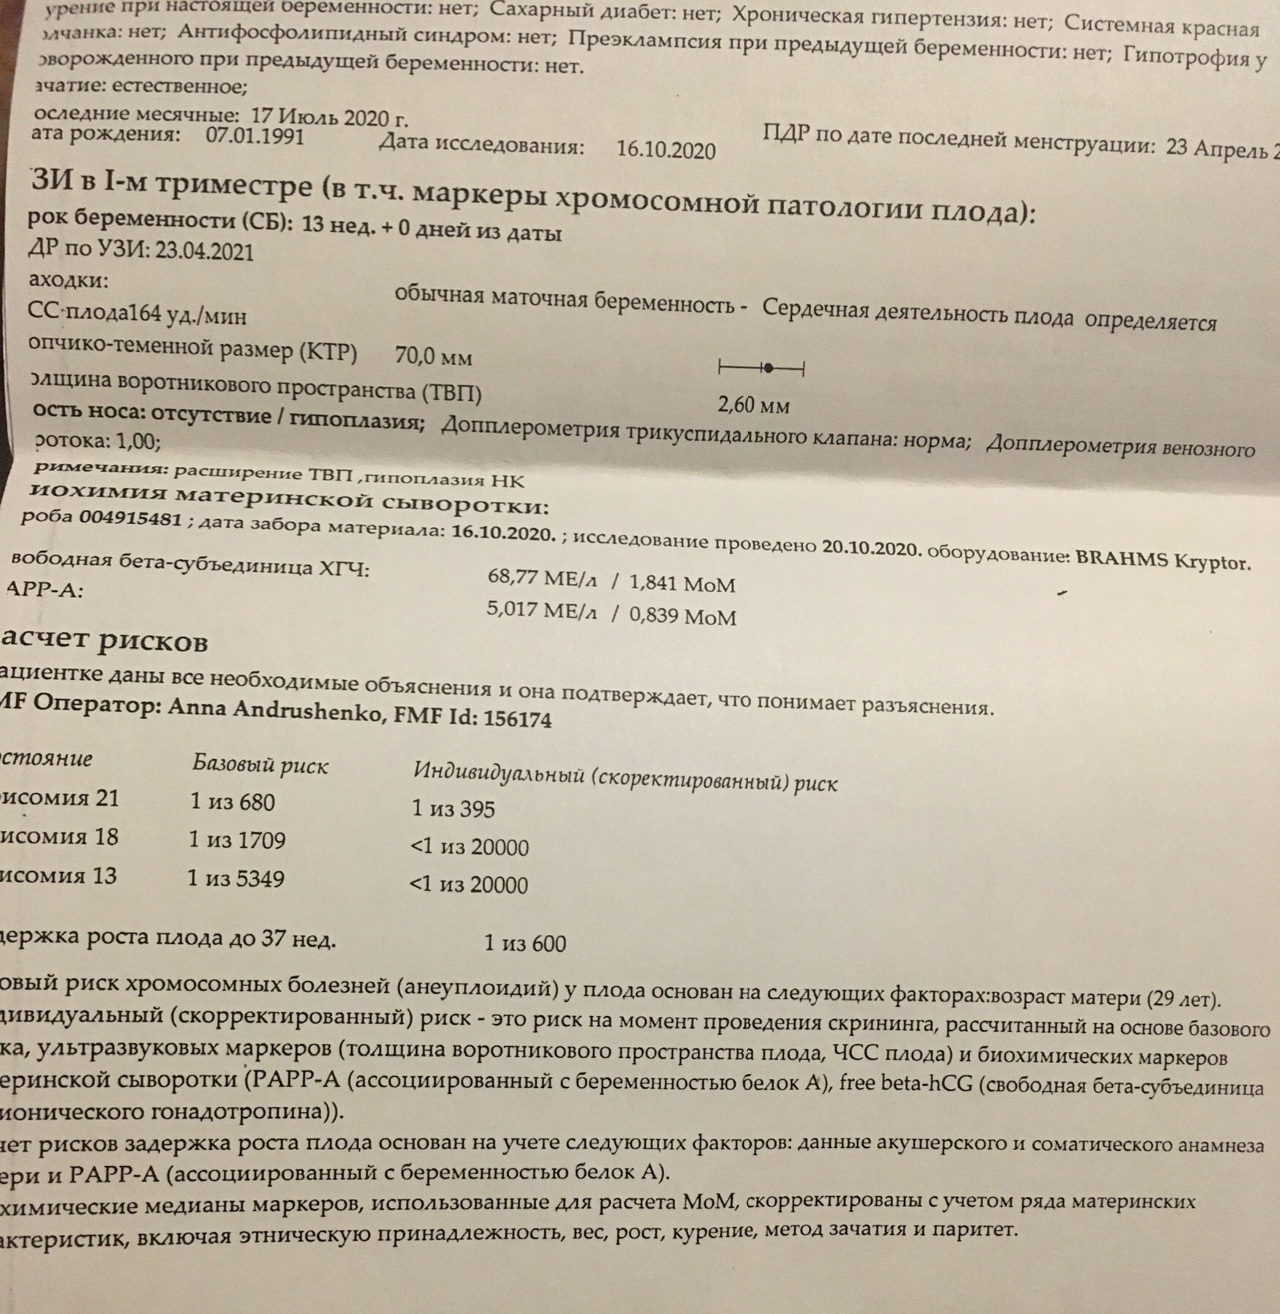

Первый скрининг УЗИ на 13 неделе: Что нужно знать